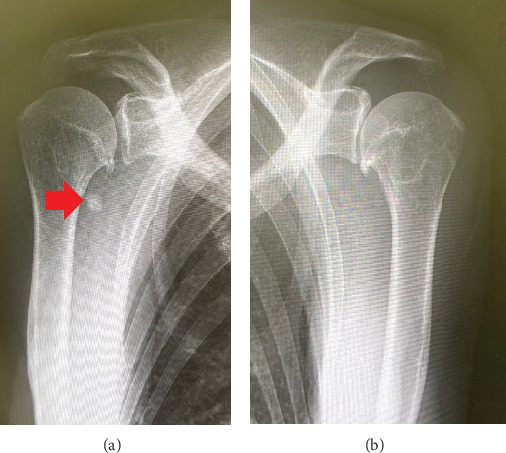

我们报告一个不寻常的病例腱鞘巨细胞瘤(TGCT)的患者谁接受了全膝关节置换术(TKA)内侧膝骨关节炎滑膜骨软骨瘤病(SO)。一位72岁的女性接受了传统的基于夹钳的双侧双交叉肌稳定TKA。术后四年,患者以仅右膝持续性疼痛为主诉来我院就诊,并伴有复发性自发性关节出血。我们进行了滑膜切除术,开放切除清创和聚乙烯交换。滑膜标本的组织学分析与TGCT一致。我们报告第一例TKA后SO背景下发生的新生TGCT的影像学和病理细节。

We report an unusual case of a tenosynovial giant cell tumor (TGCT) in a patient who received a total knee arthroplasty (TKA) for medial knee osteoarthritis with synovial osteochondromatosis (SO). A 72-year-old woman underwent conventional jig-based simultaneous bilateral bicruciate-stabilized TKA. Four years after the surgery, she came to our hospital with a chief complaint of persistent pain in the right knee only, with recurrent spontaneous hemarthrosis. We performed a synovectomy with open excisional debridement and a polyethylene exchange. Histologic analysis of synovial samples was consistent with TGCT. We present the imaging and pathological details of the first case of de novo TGCT that occurred in the background of SO after TKA.